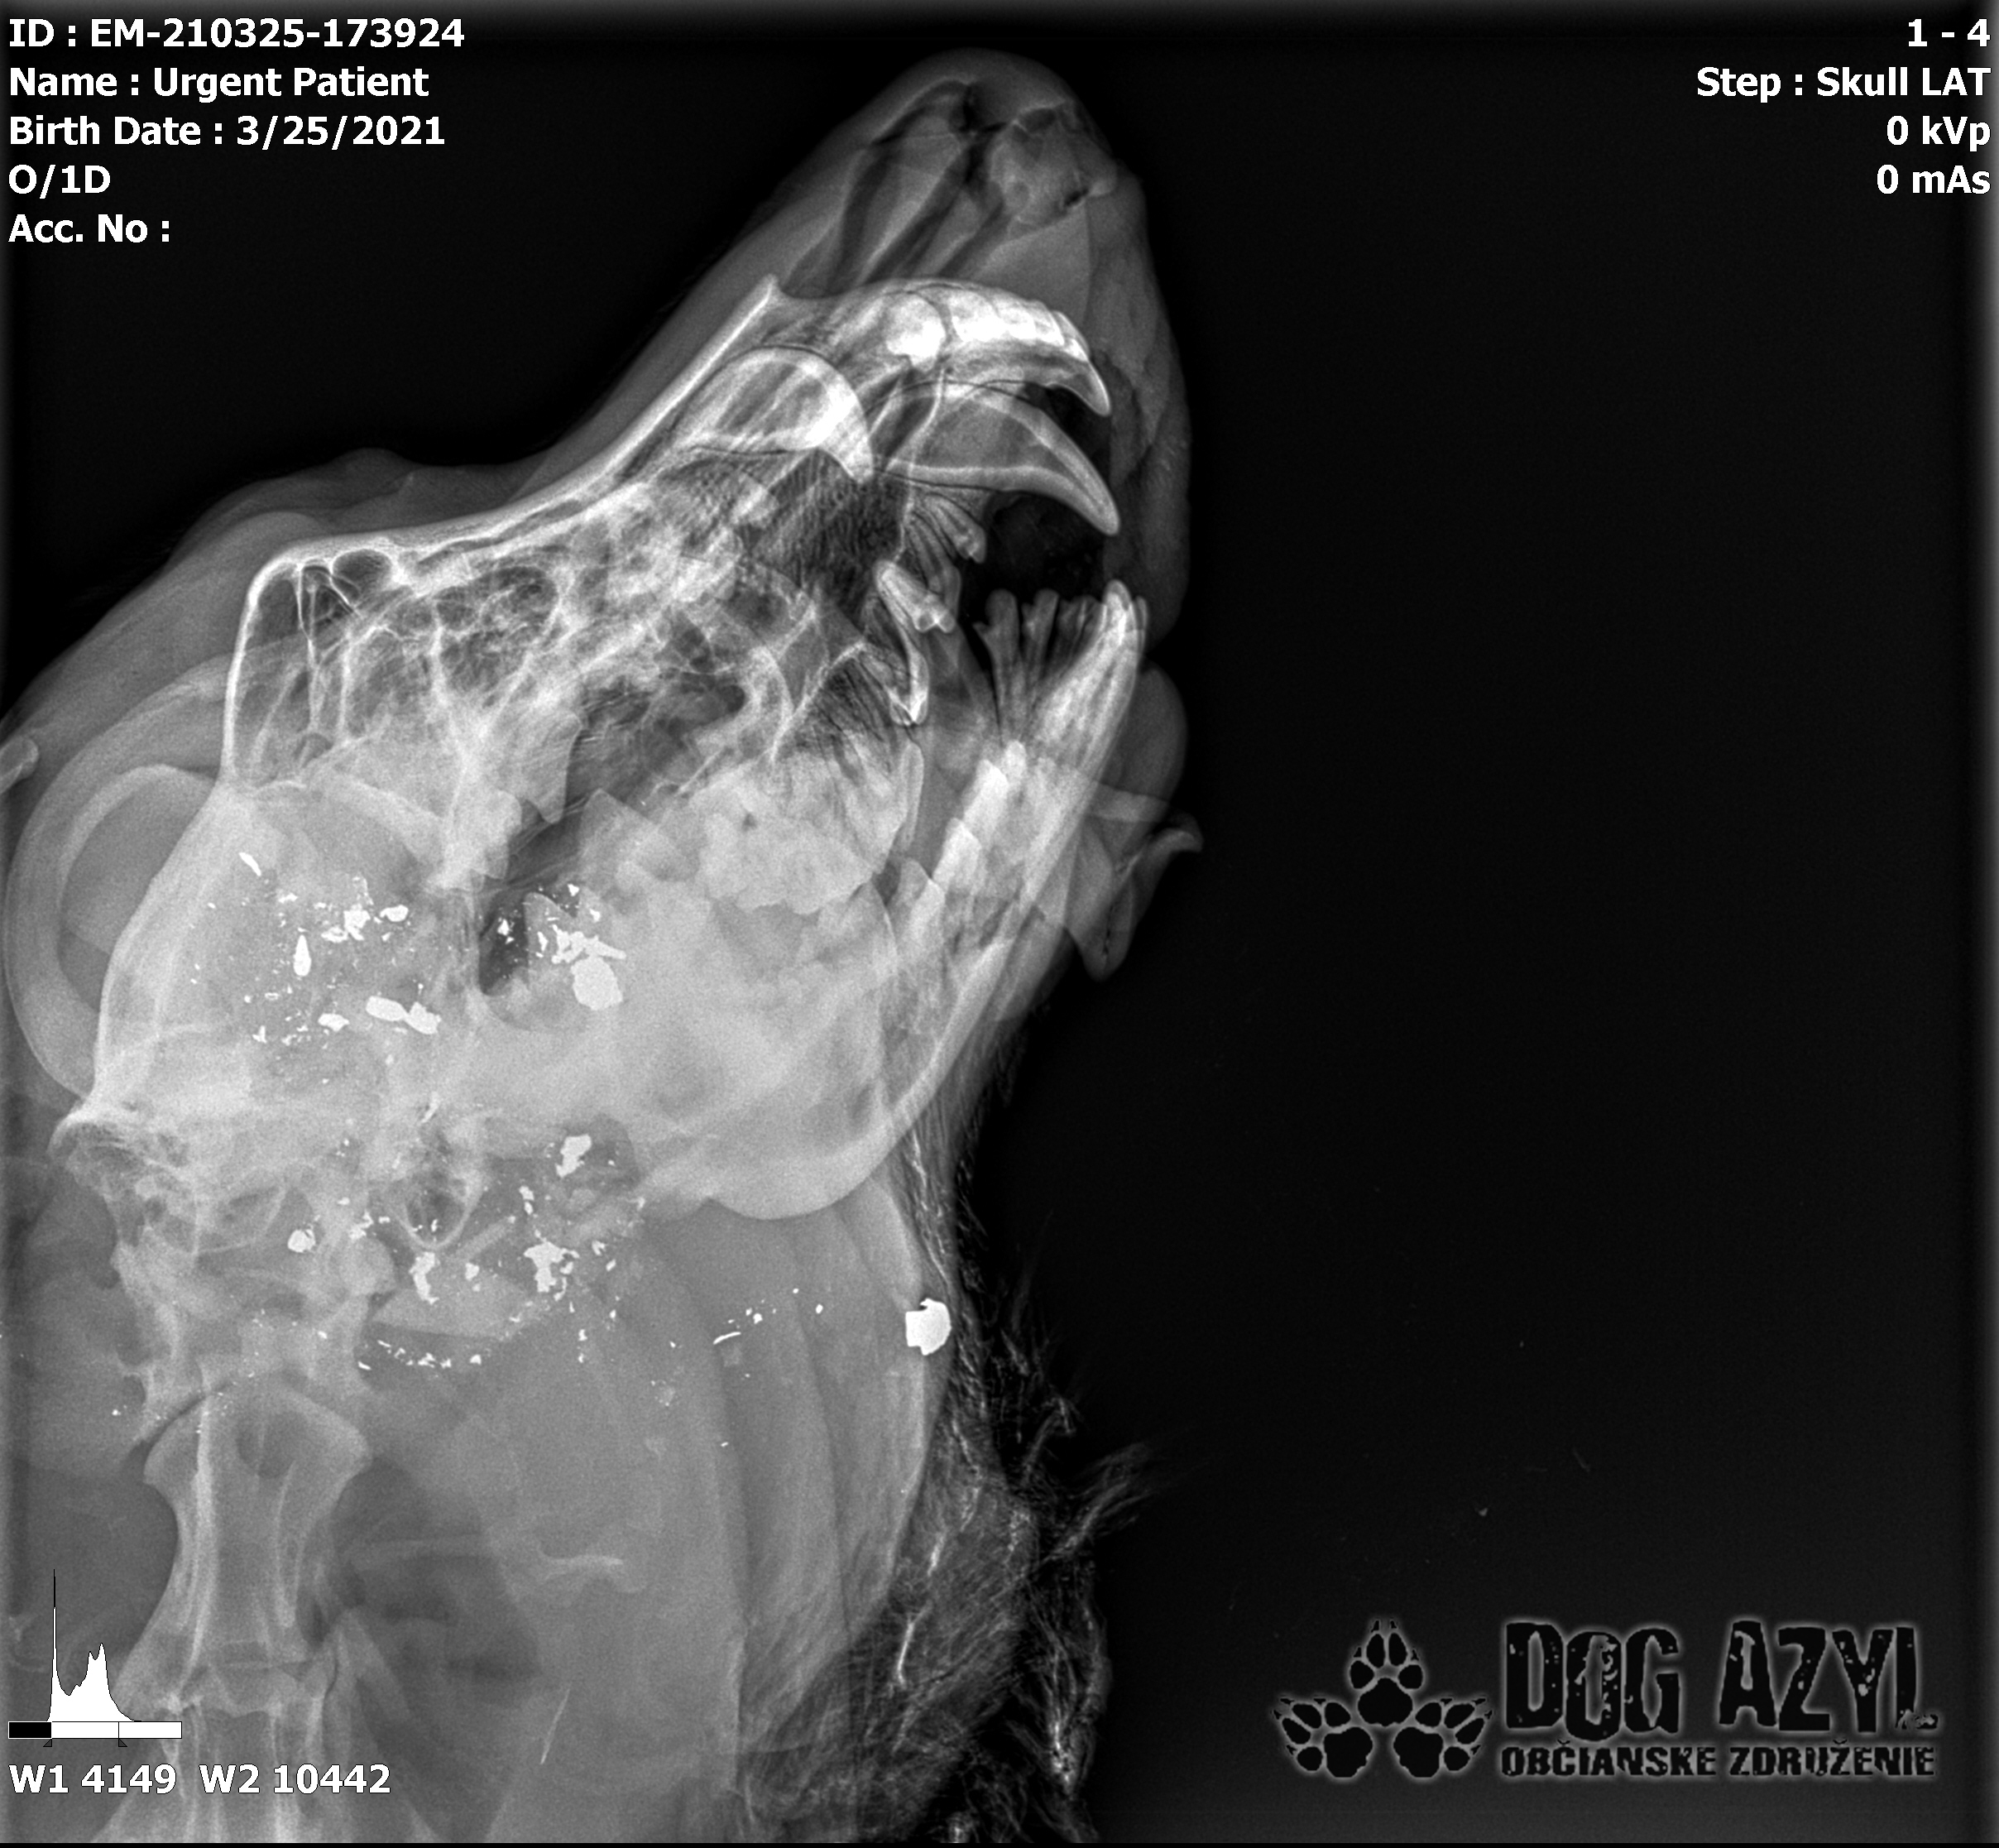

Ona ležala na ľavo, on na pravo od zavesenej šunky, ktorá mala zrejme slúžiť ako návnada, aby sa terče nehýbali.. Uprostred ničoho, bez svedkov, bez dôkazov... Pár kvapiek krvi na ceste.. Ona to schytala jedinou ranou do srdca.. On má roztrieštenú sánku, schytal to do hlavy..

/Strašne to chcem dopísať tak, aby to bolo čitateľné a pochopiteľné, ale celá sa klepem od zlosti a nevidím cez slzy.../ Lebo Ona už meno nikdy nebude mať.. On dostal meno Baris a bojuje o život!!! Má dolámanú sánku a je v šoku!!! Dostal prvú pomoc, analgetiká a priorita bola znížiť jeho teplotu z 41,4°C!!!

Ústami nevie pohnúť, jazyk si nevie ovládať a tak sa sám nedokáže schladiť ani napiť. Podľa RTG sú srdiečko a pľúca v poriadku, ale vôbec nemá vyhraté!!! Niekto chcel Barisa zlikvidovať, ale my za neho budeme bojovať do posledného dychu!!! Zajtra bude prevezený na veterinárnu kliniku Sibra centrum, kde ho čaká team špecialistov z oblasti chirurgie, neurológie a ortopédie. Ak je čo i len najmenšia nádej, že Baris bude môcť žiť, tak BARIS BUDE ŽIŤ!!!